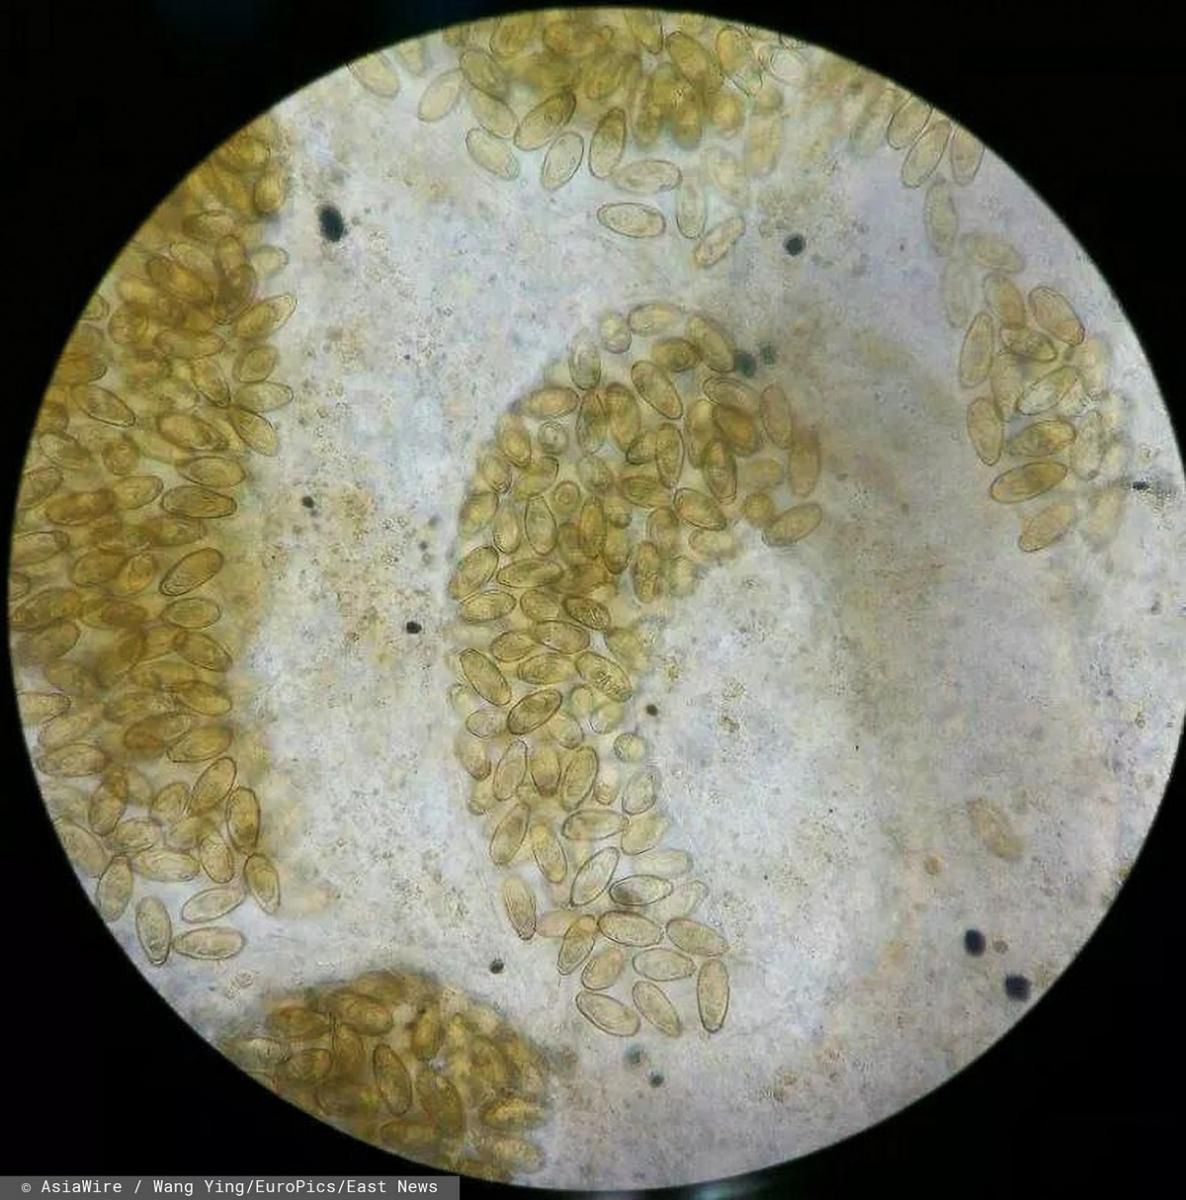

Konieczna okazała się kolejna operacja. W końcu lekarze usunęli mężczyźnie pół wątroby. Późniejsze badania wykazały, że obumarła tkanka wyciętego organu miała "niezliczone jaja pasożytów".

Jaja pasożyty na wątrobie

Jaja pasożyty na wątrobie © East News

Ostatecznie lekarze zdiagnozowali u mężczyzny klonorchozę. Tę chorobę wywołują pasożyty o nazwie przywra chińska (Clonorchis sinensis). Jak się okazało - mężczyzna jadł yusheng – sałatkę z surowej ryby w stylu kantońskim. Ta lokalna potrawa zwykle składa się z pasków surowej ryby zmieszanych z rozdrobnionymi warzywami oraz różnymi sosami i przyprawami. W ten sposób jaja przywry dostały się do przewodu pokarmowego, a następnie zaatakowały wątrobę 55-latka.